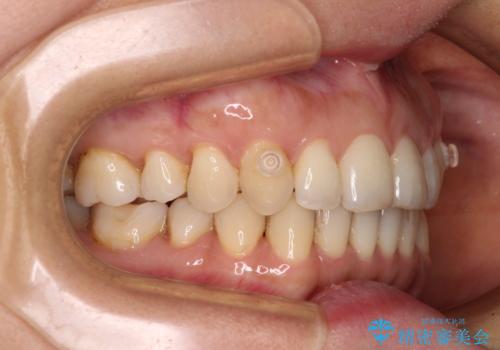

矯正治療の後戻り インビザライン・ライトによる矯正治療

- 患者様

- 40代女性

- 矯正装置

- インビザライン・ライト

- 治療期間

- 11ヶ月

- 矯正治療の後戻りを気にして来院された患者様です。

後戻りは軽微であったので、インビザライン・ライトにより矯正治療を行うこととしました。